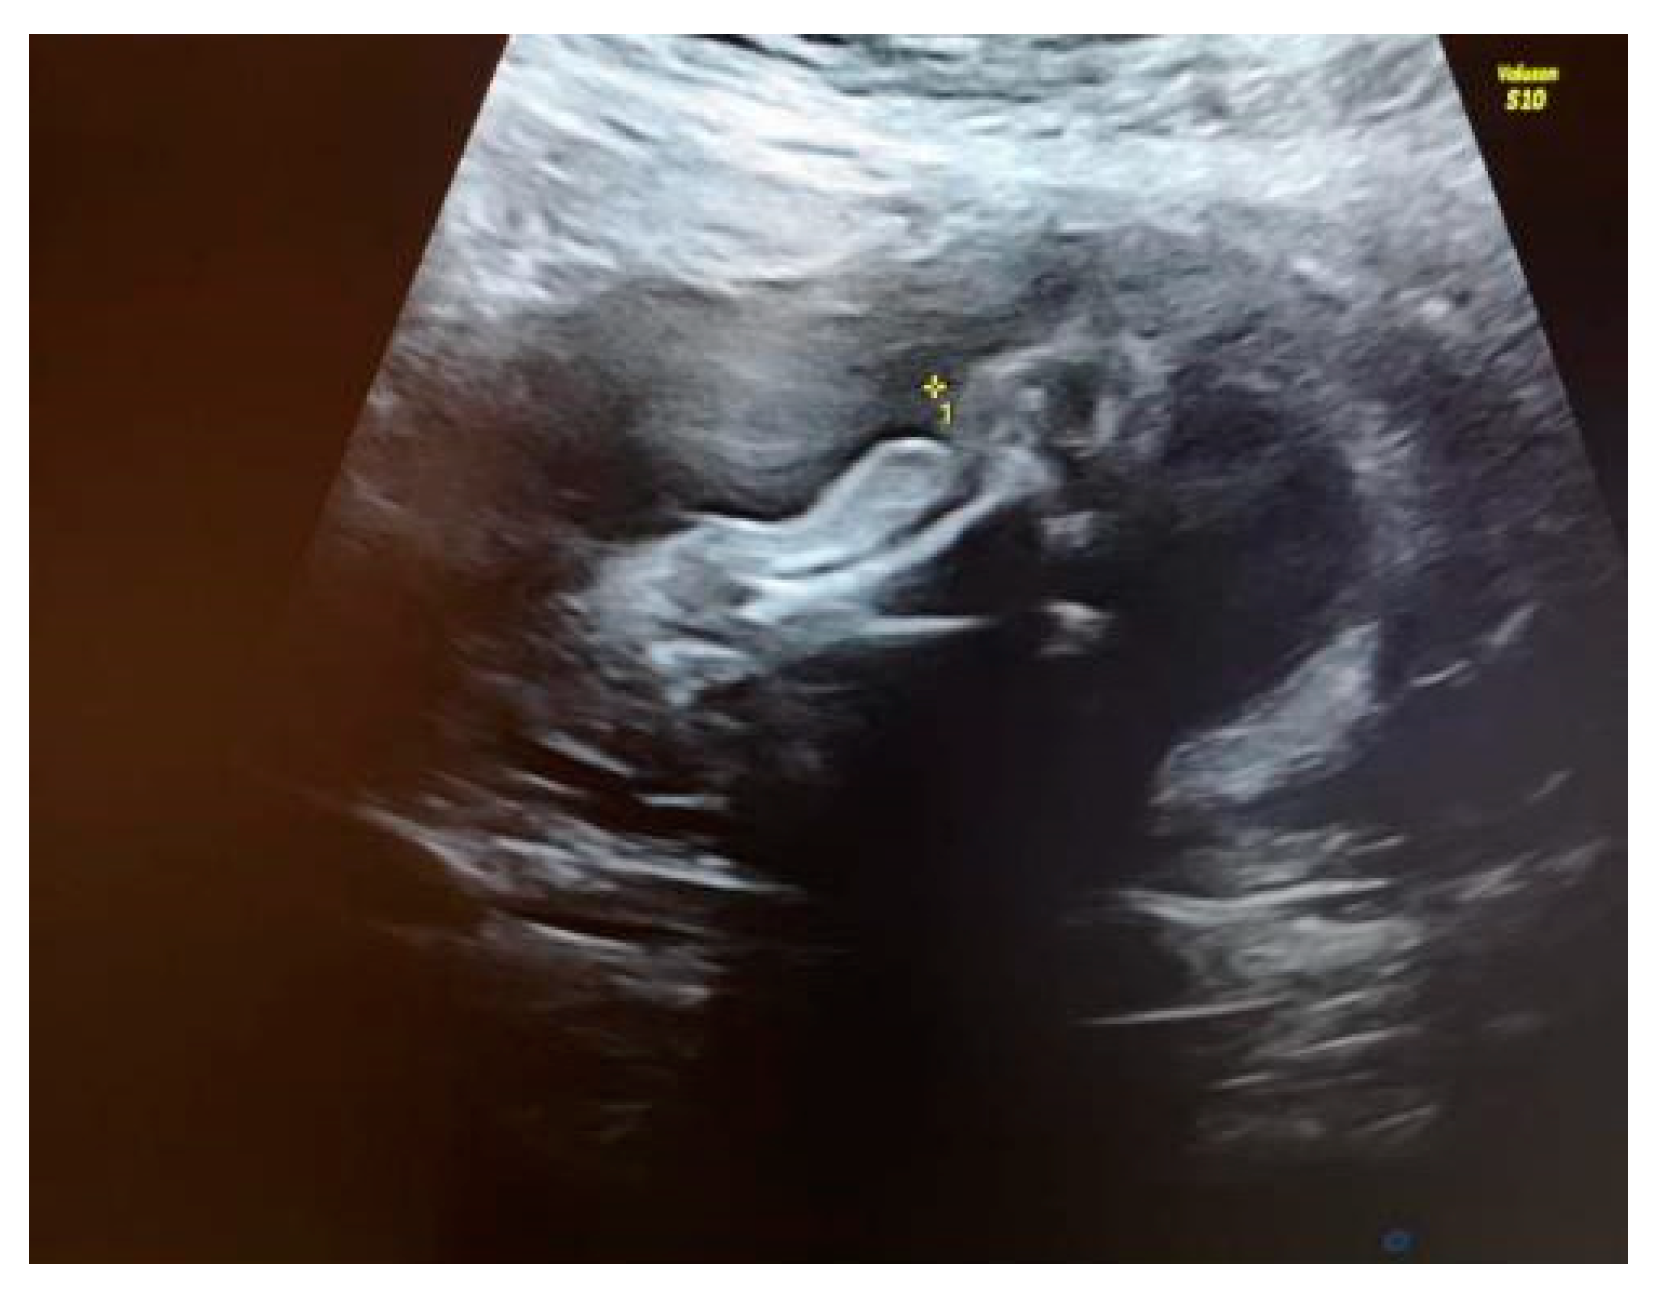

Our ultrasound examination revealed a normally grown female fetus, with an abnormal development of the right lower extremity. The right femur measured within normal ranges for the gestational age. There were flexion/extension movements at the level of the knee joint. Just below the right knee, the right leg appeared shorter and thinner than the contralateral one. The tibia and fibula from the right shin were below the third centile, with a mild curvature (see Figure 1a). Above the right knee, at the level of the right thigh, there was skin oedema. The right foot was shorter, and it had an abnormal shape (see Figure 1b). The rest of fetal anatomy appeared unremarkable, and in particular, the spine, ribs, upper extremities and left lower extremity had no additional changes.

We explained to the parents that this anomaly was isolated. Because of the unilaterality of the defect, it was less likely that this was associated with underlying chromosomal abnormalities or genetic syndromes. The amniocentesis results showed a normal karyotype and normal array CGH. Our diagnosis was amniotic band syndrome. This is a rare finding when a fibrous amniotic band entangles parts of the fetus and constrict the blood supply to a specific part and causes the deformity of different parts of the fetus (see Figure 2).

Figure 2. Visualization of the constricted area of the right shin.